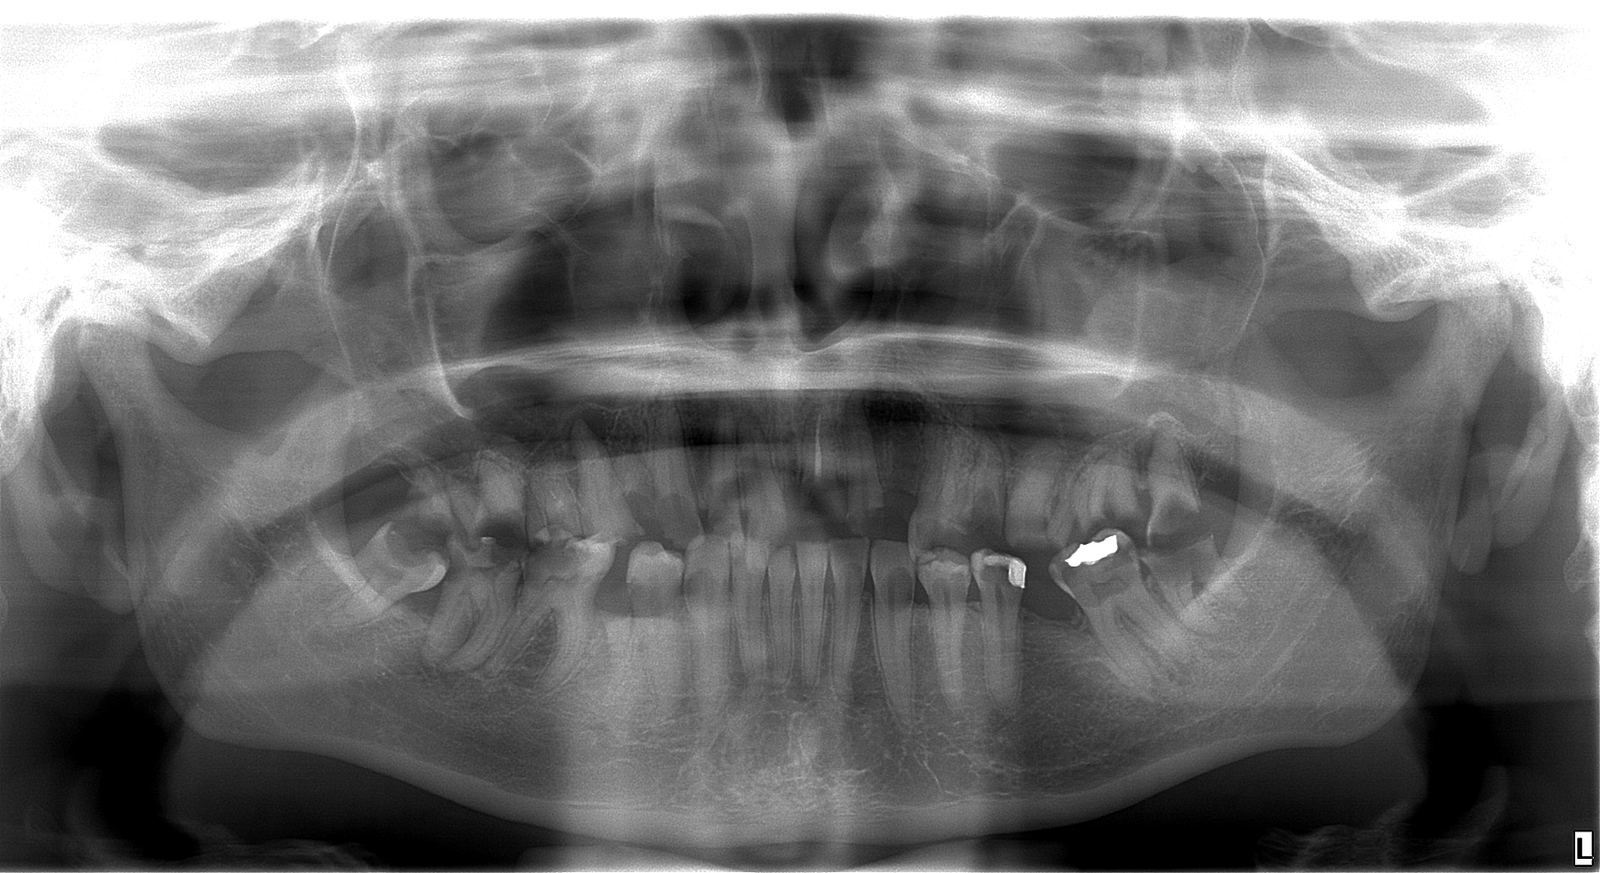

Snímka pacientky pred ošetrením

Adriana bola mladá žena, ktorá sa roky trápila s nekompletným a pokazeným chrupom. Hanbila sa smiať, vyhýbala sa foteniu a spoločnosti a spoločenským aktivitám. Rozhodla sa to zmeniť a prišla k nám. Po dôkladnej konzultácii, röntgene a 3D snímke sme jej navrhli plán na mieru: extrakcie nevyhovujúcich zubov, 6 implantátov hore, 6 dole a nový, 12-členný mostík do oboch čeľustí.